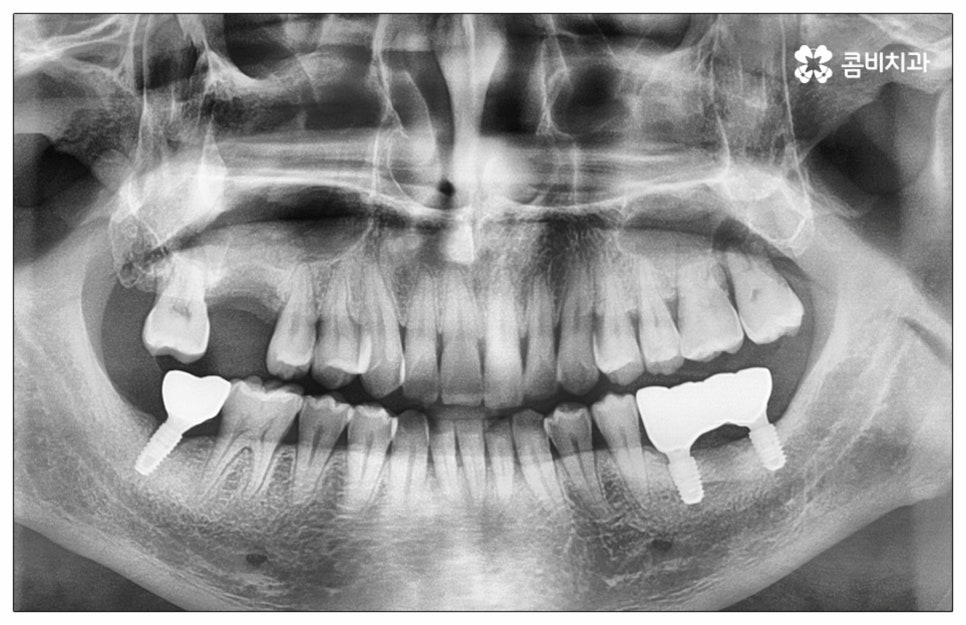

예전에는 이런 상황에서 틀니를 많이 이용하였으나 저작력 회복이 본래 자신의 치아 대비 20~30% 정도 밖에 되지 않고 잦은 탈락 위험 및 이물감, 잇몸을 눌러 장기적으로 잇몸뼈가 내려앉을 수 있다는 점 등 여러 가지 불편함이 있어 요즘은 임플란트 시술을 선호하시는 분들이 더 많아지고 있어요. 임플란트란 인체에 무해하며 잇몸뼈와 잘 결합하는 인공 치근을 잇몸뼈에 직접 식립하고 그 위로 기둥이 되는 중간 지대주와 치아 머리가 되는 크라운 보철물을 연결하여 인공 치아를 만들어 주는 시술을 말하는데, 자연 치아의 80% 정도 저작력 회복이 가능하기 때문에 식사를 할 때 음식을 크게 가리지 않아도 된다는 점 그리고 심미적으로 봤을 때 주변 치아와 자연스럽게 어우러진다는 점 때문에 각광을 받고 있습니다. 게다가 건강 보험 가입자이면서 만 65세 이상 부분 무치악 환자라면 평생 임플란트 2개까지 보험 적용을 받아 비용 부담을 줄일 수 있기 때문에 더욱 더 수요가 늘어나 이제는 치아 상실에 대체하는 대표적인 방법으로 임플란트 시술이 꼽히고 있는데요.

많이 대중화 되었다고 해도 임플란트 수술 자체가 술자의 숙련도에 크게 영향을 받는 복잡하고 고난도의 진료인 것은 틀림이 없기 때문에 담당 의료진이 해당 분야 임상 경험이 풍부한지, 뛰어난 기술력과 노하우를 가지고 있는지 꼼꼼하게 체크해 보실 필요가 있어요. 특히 노년층의 경우 당뇨, 고혈압 등 만성 질환을 앓고 있는 경우가 많아 혹시 상시 복용하고 있는 약이 있는지, 현재 환자 개개인의 상태는 어떤지, 사전 처치가 필요한 부분은 없는지 등등 수술 조건을 좀 더 까다롭게 평가한 후 환자분들과 이에 대해 충분히 상담하고 맞춤형 치료 계획을 세워 진행해야 하며 이를 위해 3D CT 와 같은 디지털 검진 장비를 통해 구강 내부 구조를 면밀하게 살피고 방대한 임상 데이터를 축적한 정품 임플란트 재료를 이용하여 연령이나 회복 정도를 살펴보면서 체력적 부담을 줄이는 방향으로 무리하지 않게 식립하는 것이 무엇보다 중요하다고 할 수 있습니다.

이때 추가 수술은 비급여 항목으로 건강보험임플란트 대상에서 제외되니 이에 대해서도 꼼꼼하게 살펴보시고 정밀 검진 후 담당 의료진과 자신의 상황에 대해서 충분하게 상담해 보시길 권유드리고 있습니다. 추가 수술의 대표적인 예로는 뼈이식 수술이 있는데요. 이것은 임플란트를 식립할 때 바탕이 되는 잇몸뼈의 높이나 폭, 밀도 등이 부족하다면 먼저 이를 보충해 주고 나서 임플란트를 심어주는 과정을 의미하며 같은 이유로 식립 성공률이나 장기적인 안정성을 높이기 위해 꼭 필요한 사전 처치, 즉 상악동 거상술 및 치주 질환 관련 수술 등을 먼저 해야 한다면 이 역시 추가 수술의 범주로 들어가니 자신의 상황에 대해서 상세하게 알아보실 필요가 있어요.